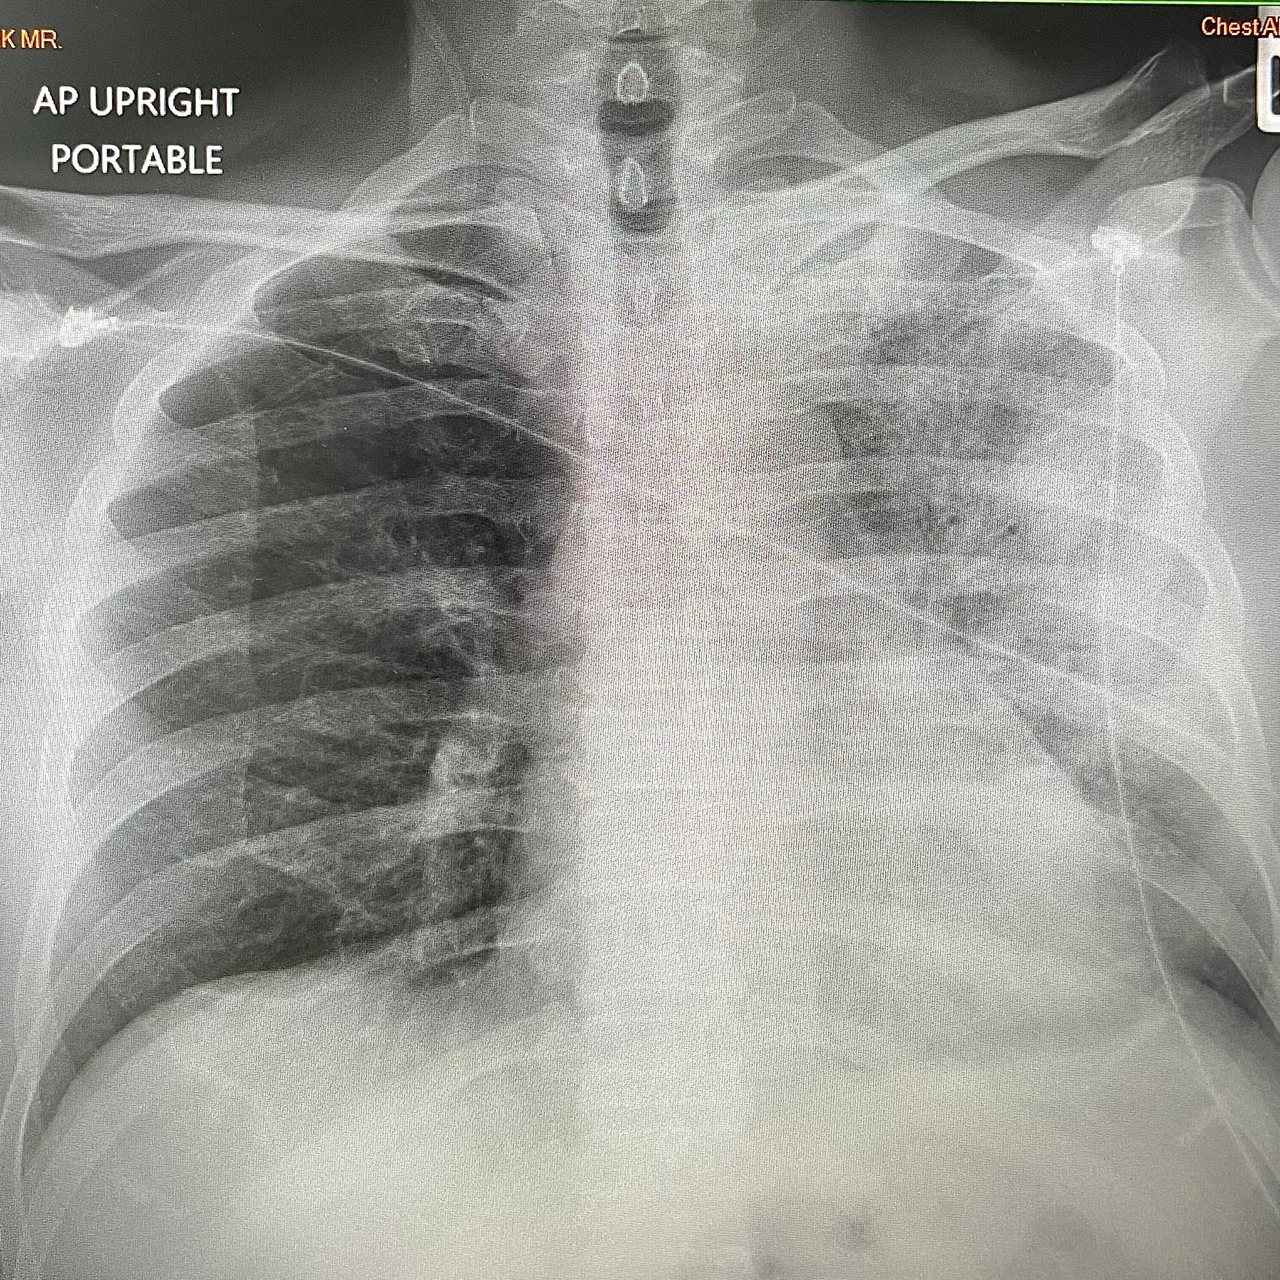

Halk arasında ‘klima hastalığı’ olarak bilinen lejyoner hastalığının tedavisindeki gecikmenin ölümcül sonuçlara sebebiyet verebildiğini söyleyen Dr. Öğr. Üyesi Esra Ergün Alış, "Lejyonella bakterisi içeren su damlacıklarının akciğere solunum yolu ile ulaşması, pnömoniye neden olur. Bu klima, jakuzi, hava nemlendirici veya sık kullanılmayan musluk, duş başlıkları yoluyla olabileceği gibi nadiren bu suların yanlışlıkla veya boğulma gibi durumlarda akciğere kaçması sonucu bulaşabilir" dedi